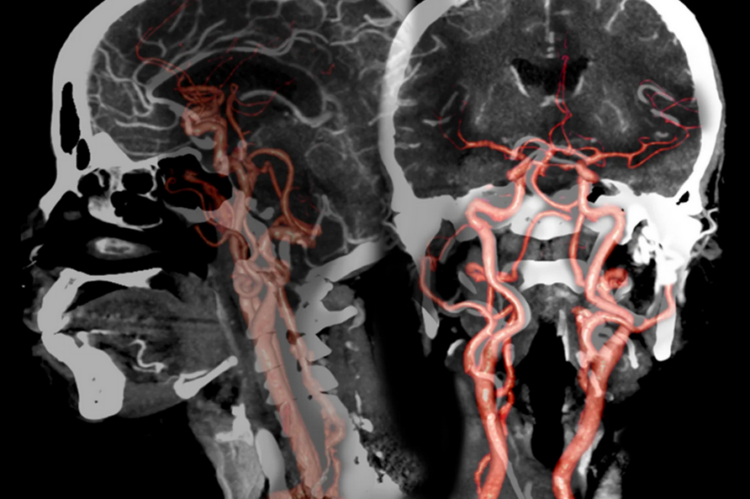

2) CT Angiography; Head/Brain

A CT angiography scan of the head/brain helps to take pictures of the blood flow in the blood vessels of the head. It can be used to look at the veins/vessels that are carrying blood to the brain.

3) CT Angiography; Head/Brain

A CT angiography scan of the neck is used to look at the blood flood through the neck and to take a closer look at the large arteries inside the neck that lead to the brain.